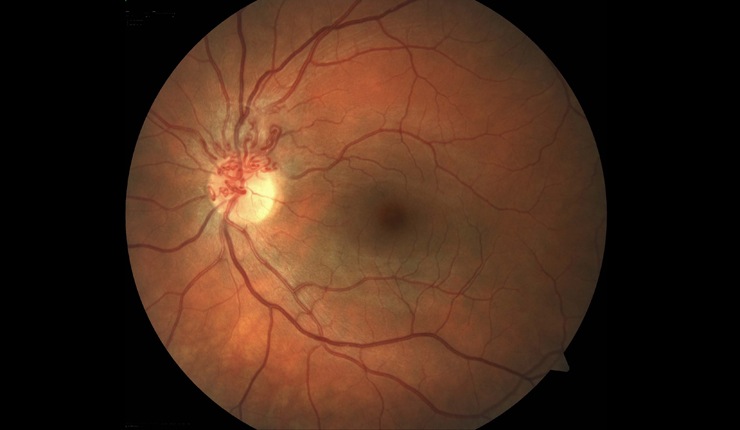

Highly reflective choroidal neovascular membrane (CNV) associated with AMD. Some residual fluid remaining at the interface of the CNV and outer retina.